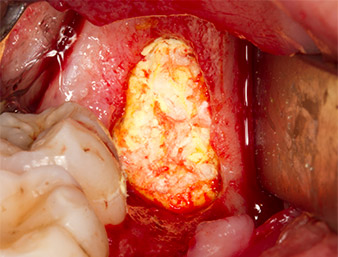

To obtain autogenous material for subsequent wound treatment, healthy bone chips were harvested from the surroundings of the root remnant with a piezo surgical instrument (Piezomed B5) (Fig. 5).

Piezomed B5

Fig. 5: Bone in the region of the alveole is lifted with a chisel-shaped piezo surgical instrument (Piezomed B5). This bone is used as autologous augmentation material after removal of the root remnant (cf. Fig. 13 and 14).

The autogenous tissue was removed with the scraper-shaped section of the working part of the instrument and stored in a physiological saline solution until further use (cf. Fig. 13).